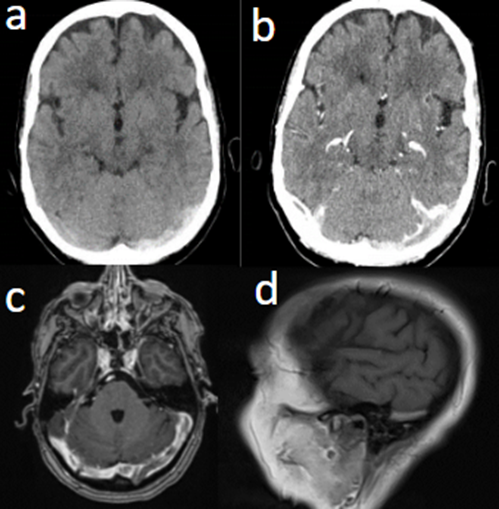

Caso del mes Noviembre 2025

Autor/Autores

Sara Septién Rivera; Josep Castell Aulet; Mildred Viveros Castaño. Área de Neurorradiología, Hospital Universitario de Bellvitge, Barcelona, España Mail: sseptien@bellvitgehospital.cat